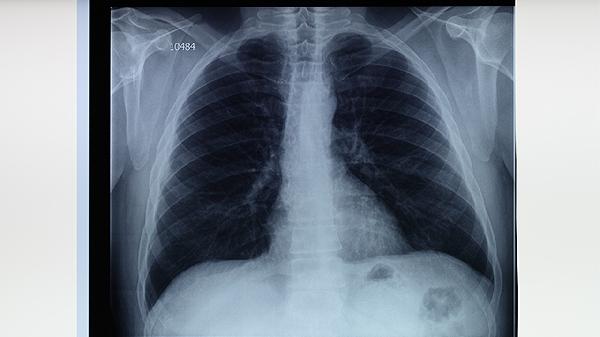

肺結核屬于什么病

是肺癌還是肺結核

肺結核有分類(lèi)嗎